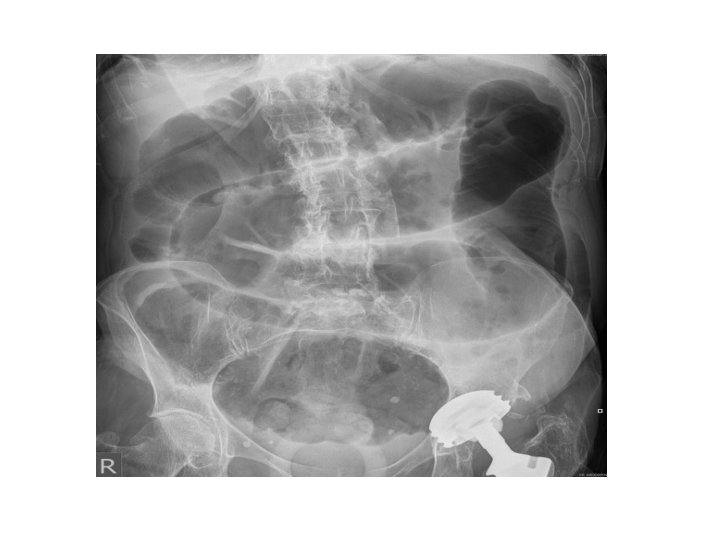

Intestinal Obstruction Supine Xray : Dilated/distended bowel loops Erect Xray : Multiple air-fluid levels Classifications: Based on Site: Small bowel or Large bowel Based on aetiopathology: Mechanical or Funtional • Based on onset : congenital or acquired • • •

Intestinal Obstruction • Congenital: anorectal malformation, intestinal atresia, congenital megacolon, congenital bands and adhesions. • Mechanical Obstruction: hernia, adhesion, volvulus, tuberculous stricture, malignancies, worm infestation, fecal impaction. • Functional Obstruction: electrolyte imbalance, spinal injuries, bowel surgeries.